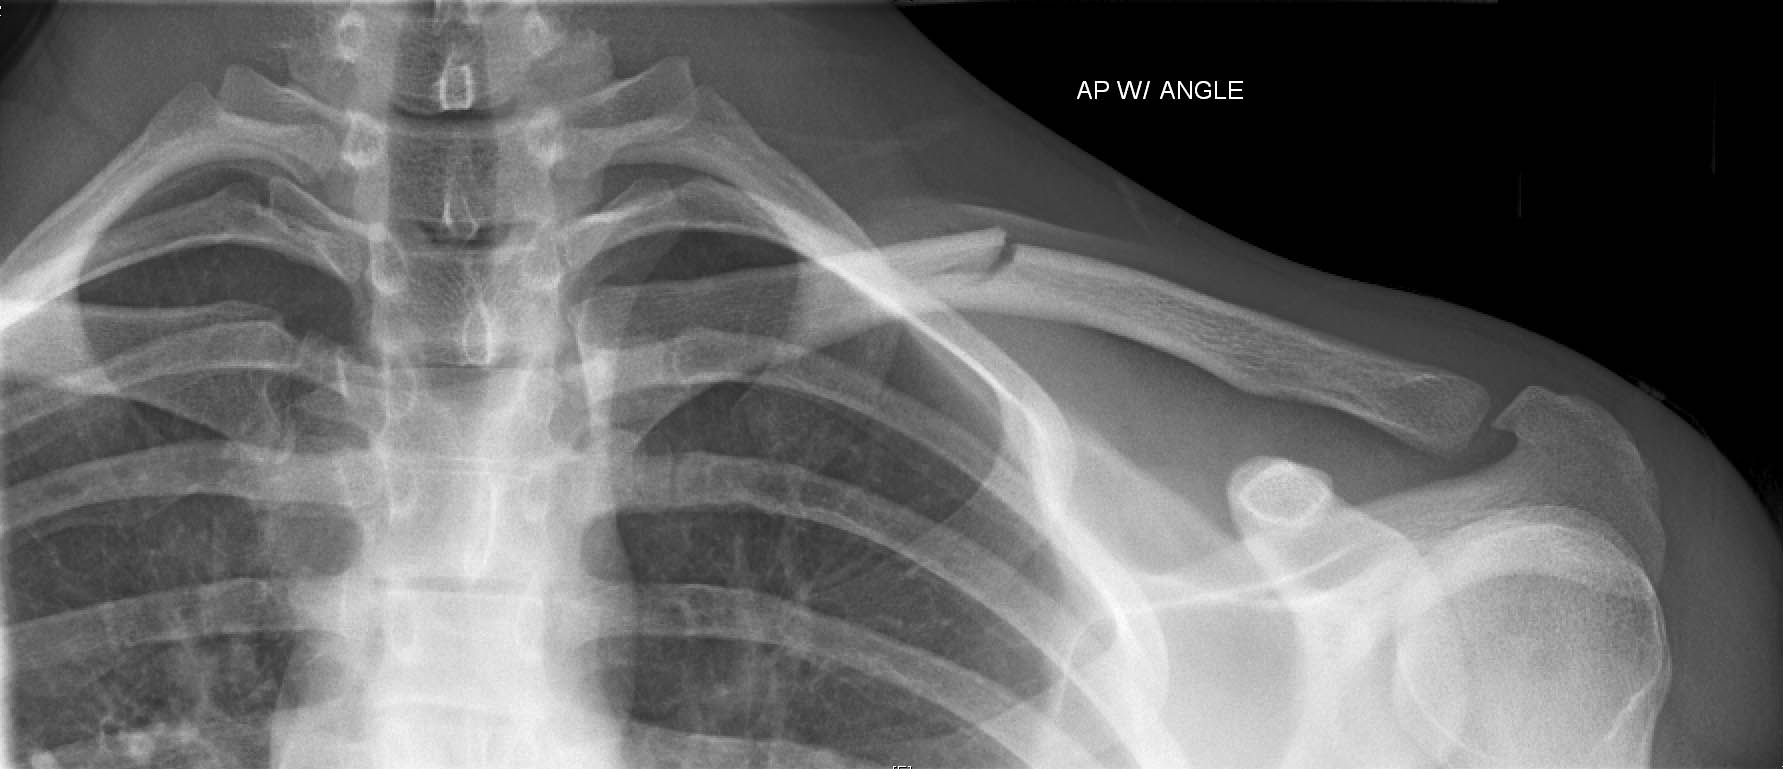

什么是新生儿锁骨骨折?该怎样护理!

新生小孩锁骨骨折怎么办?新生儿锁骨骨折是新生儿娩出过程中最常的骨折。新生儿锁骨骨折治疗简易,预后良好,没有并发症,故不应采取任何过激的治疗方法新生婴儿的锁骨骨折,大多数是产伤,而且几乎都是顺产的,这种骨折比较常见。

新生儿锁骨骨折恢复较快,一般都于骨折的一个礼拜出现骨膜增生及骨痂形成,两年内随着小儿的生长发育,肩部增宽,锁骨的畸形均可自行消失,完全恢复原状,不会留有后遗症

绝大多数新生儿锁骨骨折是不需要治疗的,只要这边的手臂穿衣服和洗澡的时候轻柔一些即可。也有的家长一直没发现,知道骨折愈合后,形成骨痂,那个地方鼓了起来,才发现,不过这个时候,孩子已经活动自如了。一般在10天左右,就会愈合,不需要任何治疗。虽然对位对线不好,愈合后有个鼓起来的包包,硬硬的,以后会慢慢塑形,包包会逐渐消失。所以是不需要担心的。